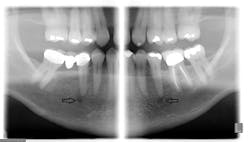

Since only the soft tissues are anesthetized by the mental block, the incisive block is preferred for nonsurgical periodontal therapy procedures. The mental foramen, which opens anteriorly and superiorly, is usually located near the apex of the second premolar (see Figure 2), although studies indicate that it can be located from the distal of the canine to the first molar.3-5 It is advisable to check the radiographs and palpate the area prior to procedures to determine its location. The foramen appears as a round or oval radiolucency on radiographs (see Figures 3, 4) and may be palpable as a concavity or rough elevation.2

Figure 3: Panoramic radiograph of right and left mental foramina. (Courtesy of Bruce Dow, DDS)